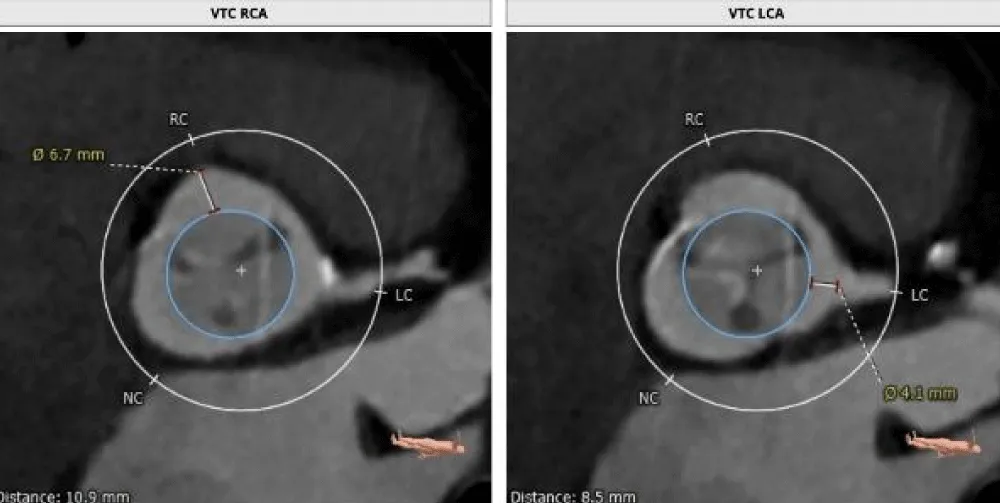

On the day of the procedure, after the patient registration process, the patient was taken to the cardiac catheterization laboratory, where she was placed under conscious sedation. The procedure was started by inserting a pigtail catheter through the left femoral artery and placing it at the non-coronary cusp of the aortic root to measure the AV hemodynamics. A temporary pacing lead wire was inserted through the left femoral vein and placed in the right ventricle. Thereafter, the LMCA was cannulated to provide coronary protection after introducing a coronary guiding catheter through the right radial artery with a straight-tip 0.014” Runthrough® coronary guidewire (Terumo Corporation, Tokyo, Japan) through a guide extension catheter (Guidezilla II; Boston Scientific Corporation, Marlborough, Massachusetts, USA) (Figure 8a-8e). The native AV was crossed using an AL-1 guiding catheter and a straight-tip guidewire (GLIDEWIRE® Standard, Terumo Corporation, Tokyo, Japan) was inserted. Thereafter, the AL-1 catheter was exchanged with a pigtail catheter and an extra-stiff supportive guidewire (Safari™; Boston Scientific Corporation, Marlborough, Massachusetts, USA) was placed in the LV apex. The 14-Fr Python Introducer sheath was advanced through the right femoral artery for the delivery of the selected 21.5 mm BE Myval valve. Pre-dilatation was performed using a 20 × 40 mm Mammoth™ over-the-wire balloon (Meril Life Sciences Pvt Ltd., Vapi, India) followed by the deployment of a 21.5 mm BE Myval THV under rapid pacing. Post-dilatation was performed by adding 1 cc extra volume to the 21.5 mm balloon of the Navigator™ THV delivery system (Meril Life Sciences Pvt Ltd., Vapi, India) that carried the crimped Myval THV. The postprocedural aortogram showed normal coronary flow and patent LMCA, while the postprocedural 2-D echocardiograph showed the mean and peak AV gradients of 10 mmHg and 18 mmHg, indicating stable hemodynamics without any aortic regurgitation or residual pressure gradient across the AV (Figure 9). Hence, the coronary guiding catheter was retracted. Both the femoral and the trans-radial access sites were closed with Perclose Proglide® suture-mediated foreclosure (Abbott Cardiovascular, Santa Clara, California, USA).

Download Image

Figure 8: a. Angiogram showing the protection of the LMCA using a guide extension catheter and a supportive coronary guidewire (black arrow) with cannulation; crossing the diseased aortic valve using an AL-1 guiding catheter and a standard straight-tip wire (blue arrow). b. Guidewire exchange using a Safari stiff wire advanced across the valve. c. Pre-dilatation performed with a 20 x 40 mm Mammoth over-the-wire balloon. d. Positioning of 21.5 mm balloon-expandable Myval THV. e. Angiogram obtained post deployment showing the patent LMCA (blue arrow).